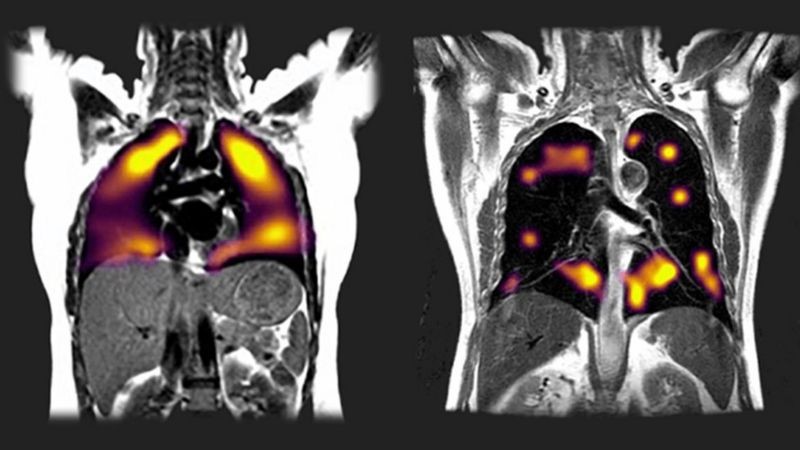

Новий метод передбачає використання газу під назвою ксенон під час МРТ для створення зображень пошкодження легенів.

Ксеноновий метод показує, як пацієнти вдихають газ під час магнітно-резонансної томографії (МРТ).

Новий метод сканування показав ознаки ураження легень, виділивши ділянки, де повітря легко не надходить в кров, у восьми осіб, які повідомили про задишку.

У легенях на фото праворуч значно більше темних плям, що свідчать про проблеми з перенесенням кисню.